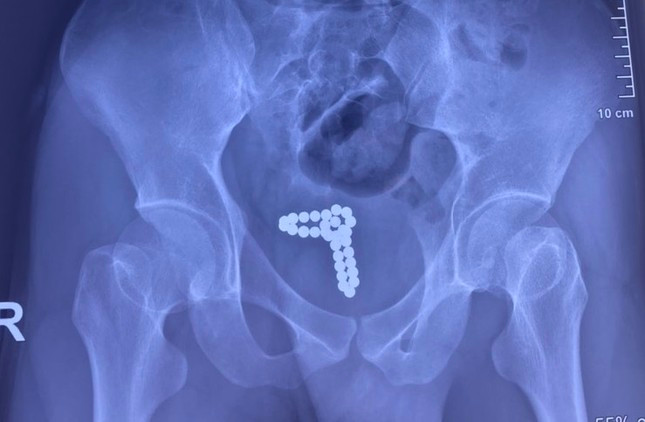

| Kết quả kiểm tra hình ảnh cho thấy, chuỗi bi kim loại nằm trong bàng quang của bệnh nhân |

Qua thăm khám lâm sàng và làm các xét nghiệm, chụp X-quang bụng, các bác sĩ Bệnh viện Nhân Dân 115 xác định dị vật là chuỗi hạt kim loại có từ tính dính với nhau thành chuỗi đang nằm trong bàng quang là nguyên nhân khiến bệnh nhân tiểu ra máu.